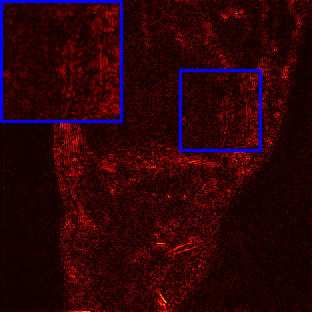

Limited by imaging systems, the reconstruction of Magnetic Resonance Imaging (MRI) images from partial measurement is essential to medical imaging research. Benefiting from the diverse and complementary information of multi-contrast MR images in different imaging modalities, multi-contrast Super-Resolution (SR) reconstruction is promising to yield SR images with higher quality. In the medical scenario, to fully visualize the lesion, radiologists are accustomed to zooming the MR images at arbitrary scales rather than using a fixed scale, as used by most MRI SR methods. In addition, existing multi-contrast MRI SR methods often require a fixed resolution for the reference image, which makes acquiring reference images difficult and imposes limitations on arbitrary scale SR tasks. To address these issues, we proposed an implicit neural representations based dual-arbitrary multi-contrast MRI super-resolution method, called Dual-ArbNet. First, we decouple the resolution of the target and reference images by a feature encoder, enabling the network to input target and reference images at arbitrary scales. Then, an implicit fusion decoder fuses the multi-contrast features and uses an Implicit Decoding Function~(IDF) to obtain the final MRI SR results. Furthermore, we introduce a curriculum learning strategy to train our network, which improves the generalization and performance of our Dual-ArbNet. Extensive experiments in two public MRI datasets demonstrate that our method outperforms state-of-the-art approaches under different scale factors and has great potential in clinical practice.